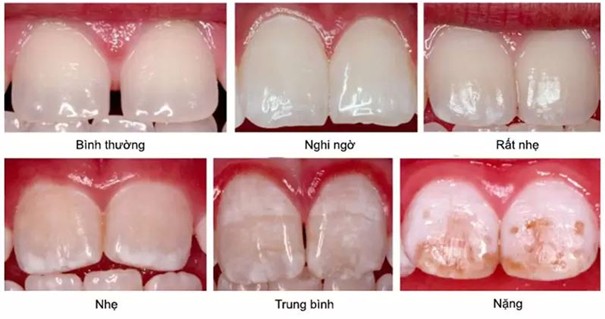

Những đốm trắng thường chẩn đoán Molar incisor hypomineralisation (viết tắt là MIH), đây là tình trạng kém khoáng hóa men răng, xuất hiện ở răng cửa hay các răng cối vĩnh viễn. Đốm trắng xảy ra theo nguyên lý: Không khí và nước bị giữ lại ở cấu trúc răng có chỉ số khúc xạ ánh sáng thấp hơn mô răng thật, dẫn đến biến đổi màu sắc. Đặc điểm của các đốm trắng là có độ trong mờ khác nhau, đa dạng về màu sắc như trắng, kem, vàng đến nâu, hay kích thước to nhỏ, tuy nhiên chỉ tổn thương lớn hơn 1mm mới có ý nghĩa chẩn đoán.

Chẩn đoán kém khoáng hóa men răng (MIH) chia thành 2 cấp độ theo tiêu chuẩn EADP năm 2010, tuỳ từng mức độ để có phương pháp điều trị phù hợp nhất.

– MIH mức độ nhẹ: Có sự thay đổi màu trắng đục trên răng cửa hay răng hàm nhưng không có sự phá huỷ men sau mọc răng, có thể nhạy cảm ê buốt với kích thích bên ngoài như không khí, nước nhưng không nhạy cảm khi đánh răng.

– MIH mức độ nặng: Màu trắng đục đồng thời có sự phá huỷ men sau mọc răng, cảm giác nhạy cảm tự phát và dai dẳng khi đánh răng và ăn nhai.

Chỉ có sự thay đổi màu sắc trắng đục như trên hình mà không bị phá hủy men răng, thì sẽ không cần mài răng, lấy tủy hay nhổ răng mà có thể dự phòng và kiểm soát triệu chứng bằng cách áp dụng phương án xâm lấn tối thiểu sau đây: Điều trị bằng nhựa xâm nhập ICON- DMG để thấm sâu và khuếch tán vào mô răng nhằm giúp nâng đỡ cấu trúc men bị mất khoáng. Từ đó dự phòng gãy vỡ men răng dưới tác động của lực ăn nhai và cải thiện các đốm trắng cho răng.